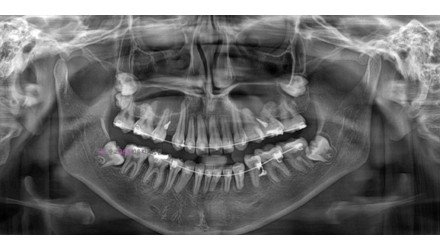

박*수 임플란트 시술 사례

전체 임플란트

해당 사진은 환자분의 동의 하에, 동일조건에서 촬영되었습니다.

모든 치료에는 환자분의 구강 상태, 생활 습관, 전신 건강 등에 따라

결과와 회복에 차이가 있을 수 있으며, 부작용이 나타날 수 있습니다.

모든 시술은 장점과 함께 부작용 가능성도 있으므로, 신중히 이해하고 결정하시길 권장드립니다.

20**.**.**

치료 전

치료 후